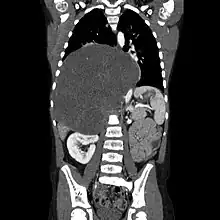

| CT scan of a large ganglioneuroma within the chest cavity | |

Ganglioneuromas most frequently occur in the abdomen, however these tumors can grow anywhere sympathetic nervous tissue is found. Other common locations include the adrenal gland, paraspinal retroperitoneum, posterior mediastinum, head, and neck.[1] It is contained within the neuroblastic tumors group, which includes:[3] Ganglioneuroma (benign), Ganglioneuroblastoma (intermediate), Neuroblastoma (aggressive).

Ganglioneuromas can be diagnosed visually by a CT scan, MRI scan, or an ultrasound of the head, abdomen, or pelvis. Blood and urine tests may be done to determine if the tumor is secreting hormones or other circulating chemicals. A biopsy of the tumor may be required to confirm the diagnosis.[4]